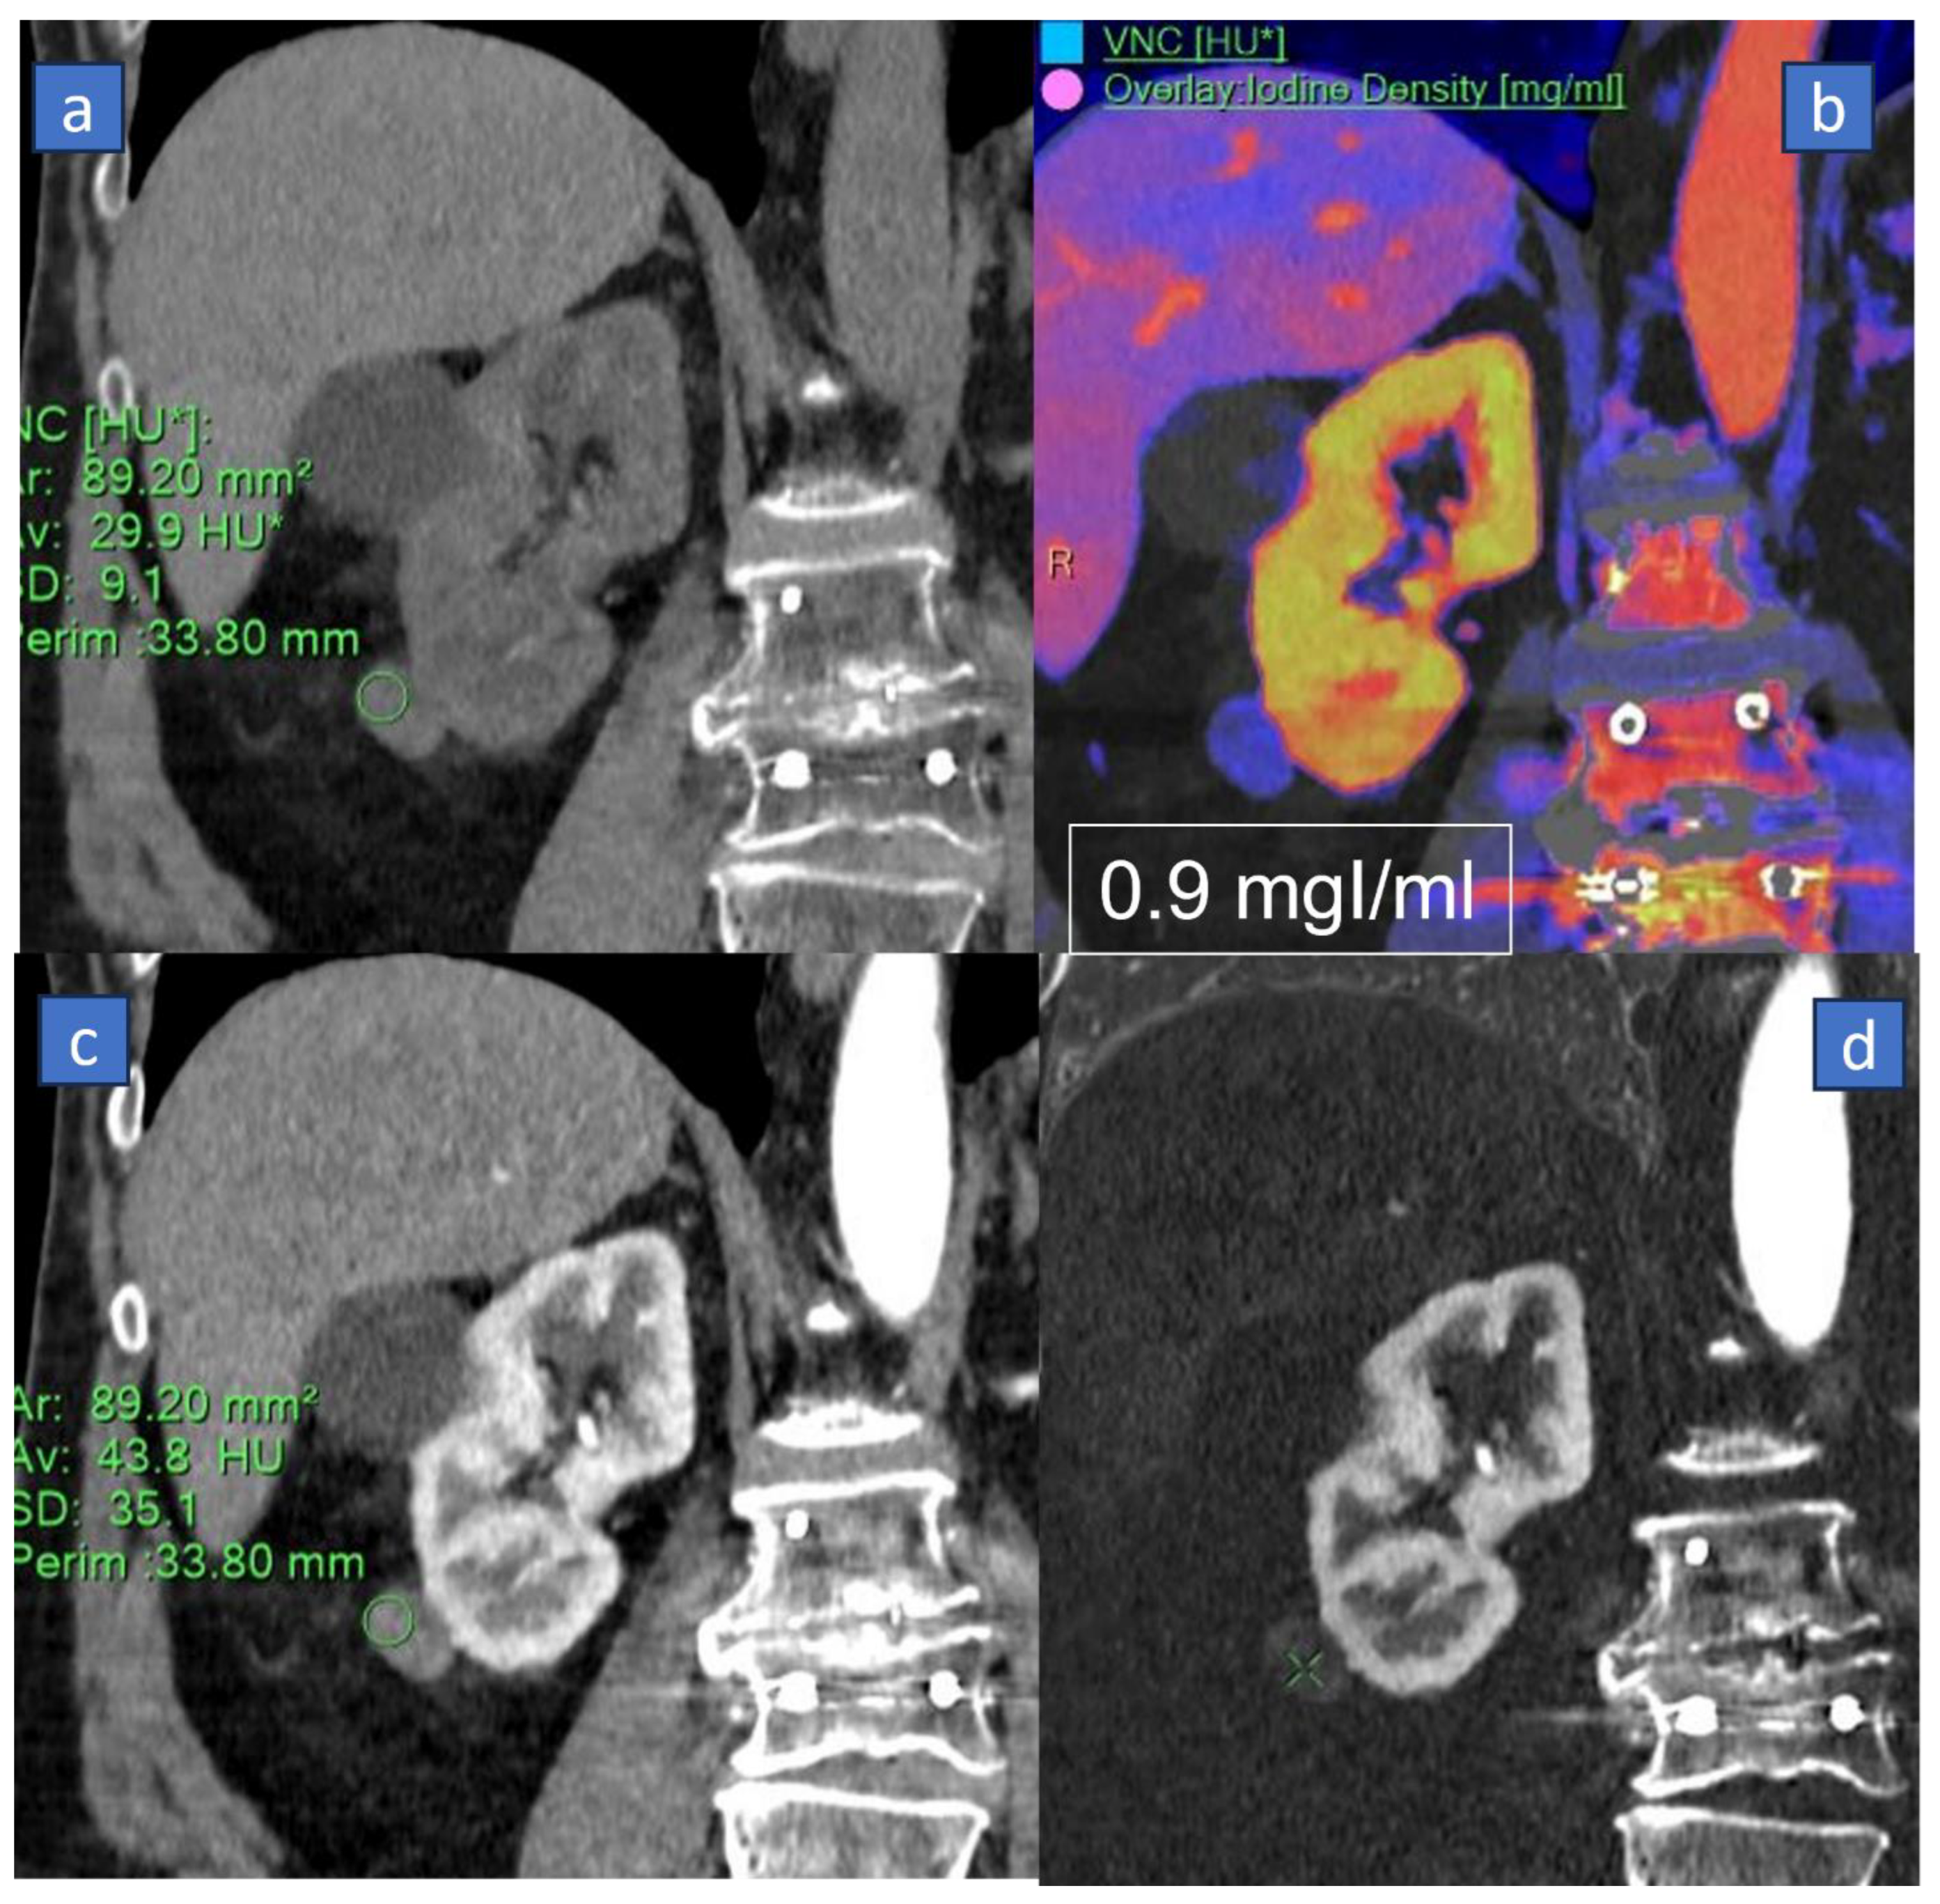

3. Iodine MAP

3.1. Applications